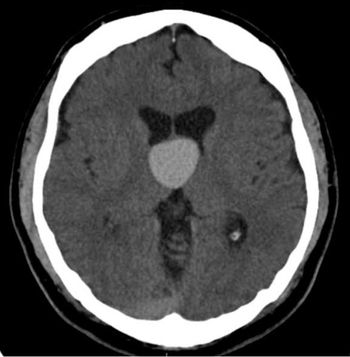

A 38-year-old male presents with headache.